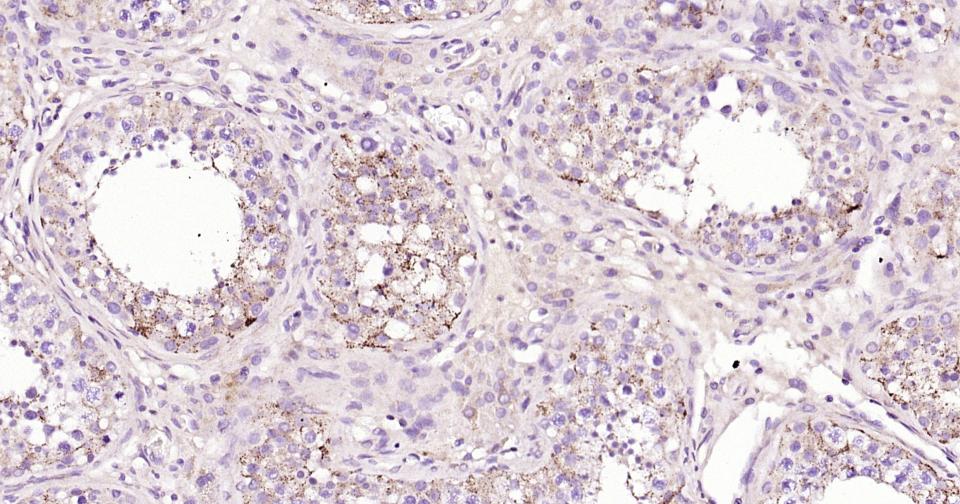

| IHC-P | Human, Mouse, Rat | 1:100-500 | |